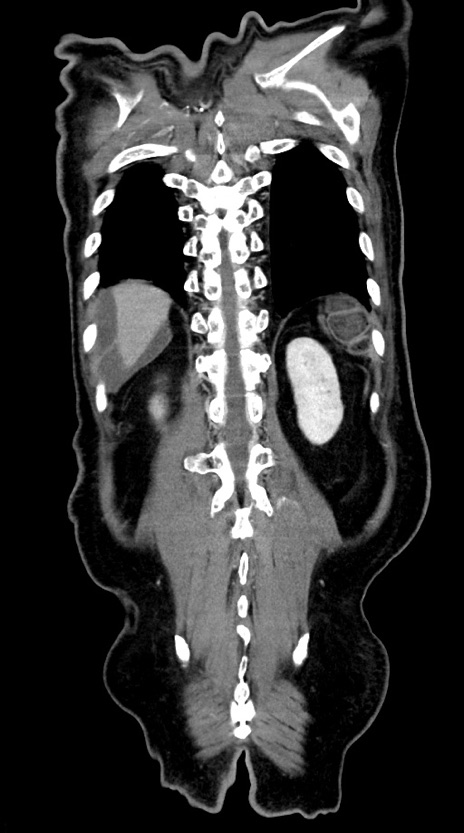

症例28(冠状断像)

【症例】60歳代男性

【主訴】嘔吐

【現病歴】胃癌にて胃全摘後。食思不振が悪化し、夜中に嘔吐することがある。

【既往歴】胃癌、胃全摘、脾摘、胆摘後

【データ】WBC 5900、CRP 10.56